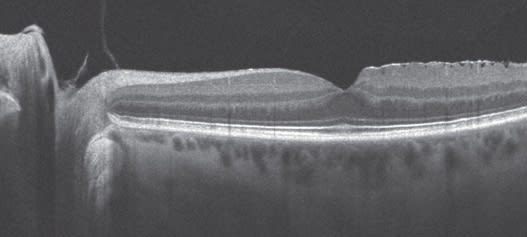

Other common entities that may be encountered during a preoperative assessment for cataract include macular hole, macular pucker and diabetic macular edema (Figures 3-5). ■

Figures 3 to 5. During preoperative assessment watch for conditions such as macular hole (top image), macular pucker (center) and diabetic macular edema (bottom).